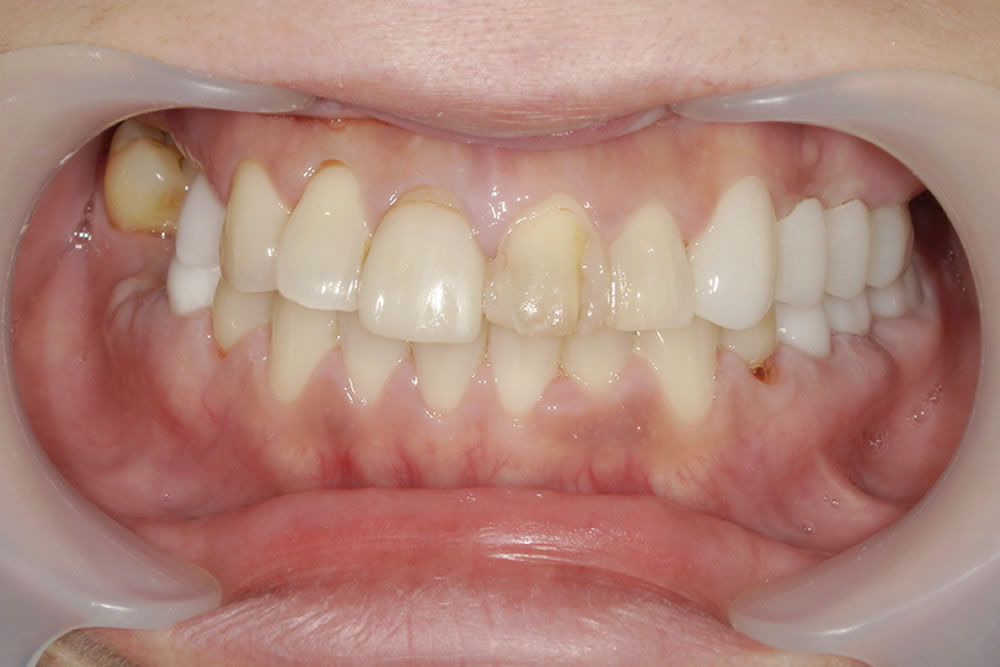

マウスピース矯正(インビザライン)で八重歯を改善した症例

年齢

30代

性別

女性

症例を見る